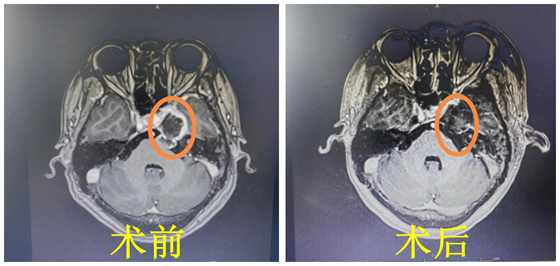

近日,来自甘肃的刘女士因四月前出现右脸麻木辗转北京上海多地求医,得到的结果是:肿瘤全切很难,特别是复发的听神经瘤,而且很大程度会面瘫。刘女士才四十多岁,不想后半生生活质量下...